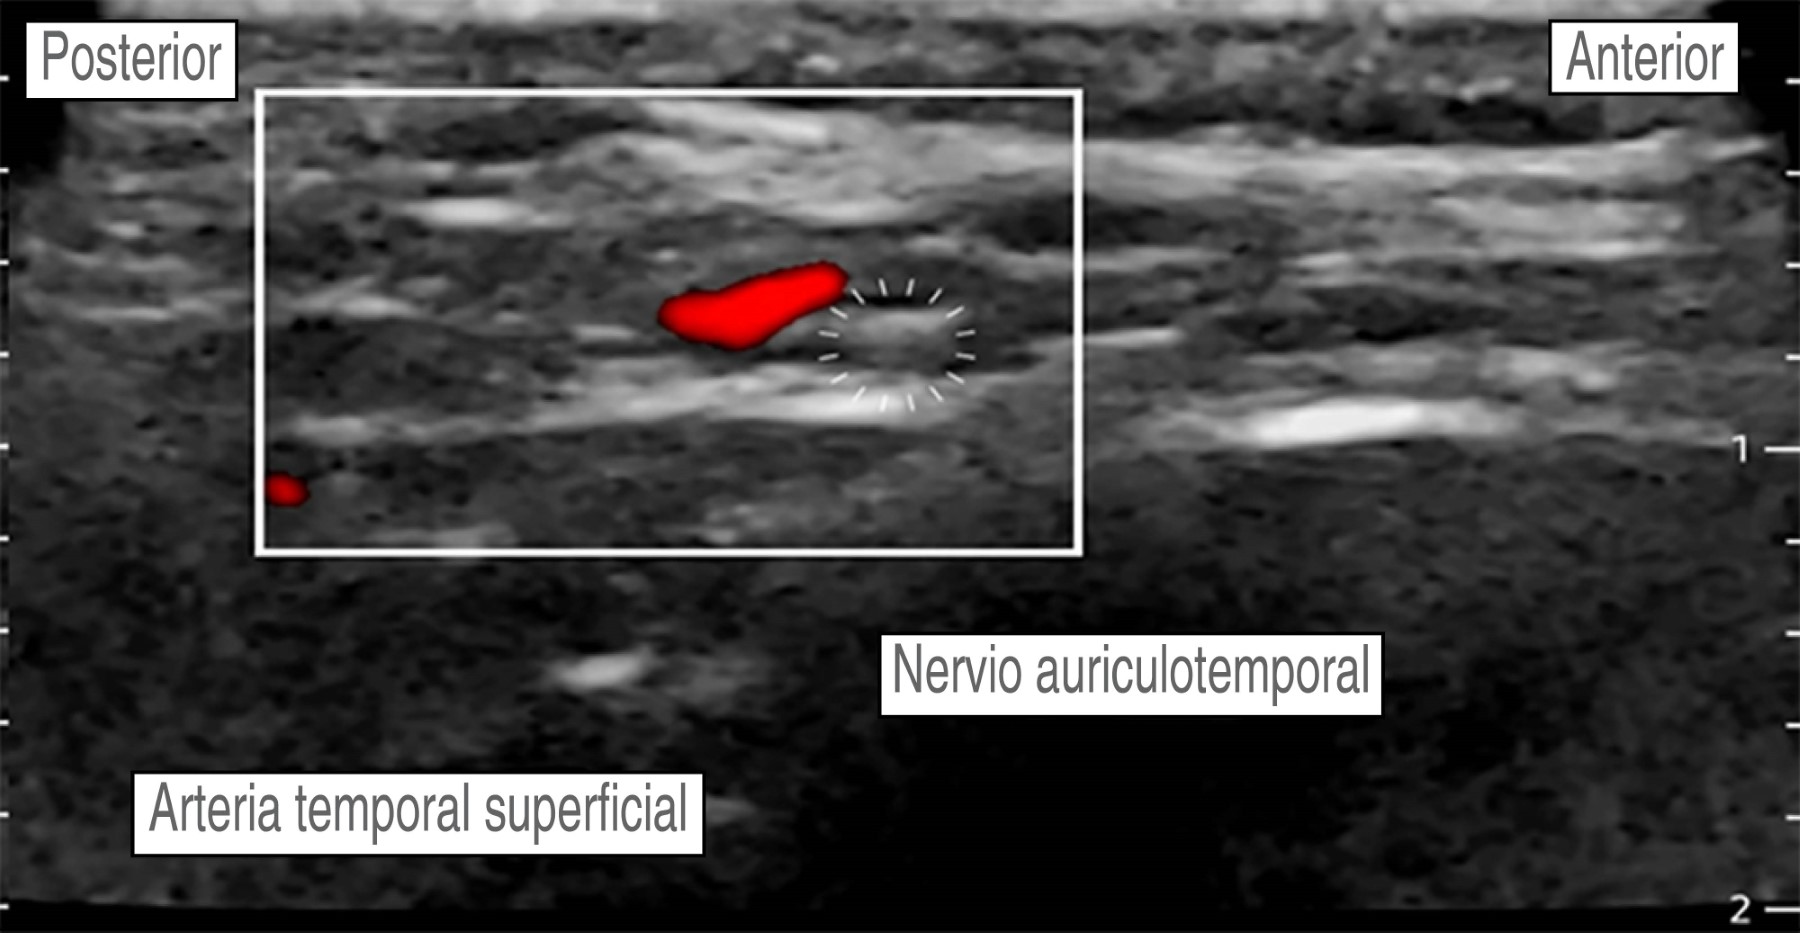

Hombre de 56 años, con diagnóstico de meningioma de la convexidad frontal, con un estado físico de la American Society of Anesthesiologists (ASA) II. Hipertensión arterial esencial en tratamiento regular con losartán 50 mg VO cada 24 horas, sin otros antecedentes. Peso: 87 kg, talla: 1.70 m. Presenta un cuadro clínico de tres meses de evolución caracterizado por cefalea holocraneana, trastornos del comportamiento (apatía, falta de motivación, indiferencia) sin datos de focalización neurológica. La imagen de resonancia magnética muestra una tumoración frontoparietal derecha de 8.2 × 5.1 cm que realza al contraste de forma homogénea, con efecto de masa significativo y desviación de la línea media de 13 mm. Ingresa a sala quirúrgica para craneotomía bifrontal y resección tumoral guiada por neuronavegación. En la sala quirúrgica bajo monitorización invasiva y anestesia total intravenosa con remifentanilo (0.15-0.2 μg/kg/min), propofol (90-120 μg/kg/min), lidocaína (1-2 mg/kg/h) y después de asegurar la vía aérea colocamos un bloqueo de escalpe guiado por USG. Se utilizó una sonda de USG lineal (10 MHz). Nervio supraorbitario y supratroclear: en situación transversal, colocamos la sonda en el hueso frontal sobre el reborde orbitario superior identificando el agujero supraorbitario (muesca). Con técnica en plano, la inyección es superficial al foramen (evitando la administración dentro del foramen), con un volumen de 1.5 mL de anestésico local, para asegurar una cobertura adecuada al nervio supratroclear colocamos otra inyección medial al supraorbitario de 1.5 mL de AL, visualizando su extensión bajo USG. No logramos identificar la arteria supraorbitaria (Figura 2). Nervio cigomático-temporal: colocamos el transductor en un plano coronal, sobre el límite anterior de la fosa temporal, posterior a la apófisis frontal del hueso cigomático, lo que nos deja visualizar tres estructuras: fascia temporal, músculo temporal y hueso temporal, colocamos dos inyecciones de 1.5 mL de AL, en dos puntos de referencia: el hueso temporal (profundo) y la fascia temporal superficial (Figura 3). Nervio auriculotemporal: en el mismo plano facial que el nervio anterior, colocando el transductor en sentido transversal entre el canto lateral del ojo y el trago, identificamos la arteria temporal superficial; el nervio corre en el mismo plano facial que la arteria y lo bloqueamos con 2 mL de AL, evitando la punción vascular (Figura 4). Nervio occipital mayor: colocamos la sonda de USG paralela a una línea que conecta el inión y la mastoides logrando identificar a la arteria occipital junto al nervio. Con inyección en plano utilizamos 2.0 mL de AL (Figura 5). Nervio auricular mayor y occipital menor: bloqueamos ambos nervios a través de un bloqueo de plexo cervical superficial, colocando la sonda transversal sobre la cara lateral del cuello, ubicando el borde posterior del músculo esternocleidomastoideo (ECM) en un punto medio entre la mastoides y la clavícula identificando el plexo como pequeños nódulos hipoecoicos profundos al borde posterior del ECM, el nervio auricular mayor se puede ver comúnmente sobre el músculo ECM. Con técnica en plano la inyección se realizó detrás del ECM, superficial a la fascia prevertebral con un volumen de 5 mL de AL (Figura 6). El bloqueo se realizó de forma bilateral utilizando 28 mL de bupivacaína isobárica a 0.5%, empleando un tiempo de 30 min, se evitó de forma efectiva la respuesta hemodinámica al pinchado, sin necesidad de aumentar la dosis de opioide, o requerir infiltración del área de colocación del pincho, se complementó la analgesia multimodal con paracetamol 1 g IV + ketoprofeno 100 mg IV, no se requirieron rescates de opioide en las 48 horas posteriores y hasta el egreso, se realizó una resección tumoral de 100% sin secuelas neurológicas, no se presentaron complicaciones asociadas al bloqueo de escalpe (punción vascular o déficit nervioso).

Figura 4